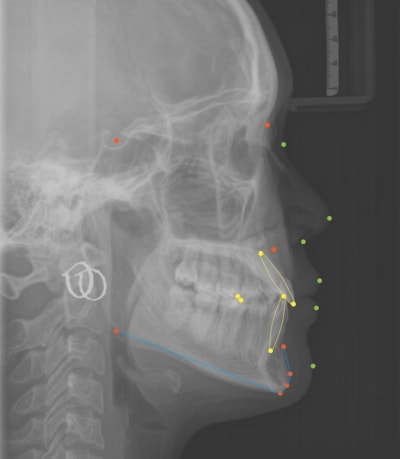

Et detection des points par IA rajouté.

J'ai due entrainer l'IA en locale sur mon PC , ça à prit quelque heure mais le résultat est impressionnant. Les points s'affiche en moins d'une seconde..

Si la détection des points est automatique, là ça devient vraiment intéressant. On ouvre le logiciel, on crée une passerelle pour récupérer les infos patients, on glisse la radio dans le logiciel, on attend 30 secondes et on a un rapport céphalométrique complet. On check si les points sont correctement placé et on valide.